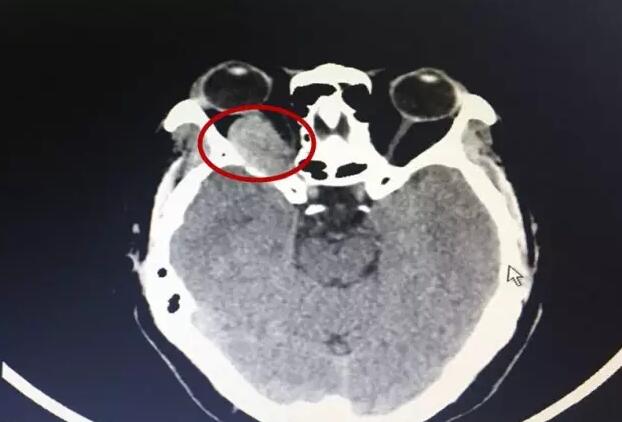

红圈处为陈阿姨的巨大眼眶肿瘤

来到福州的陈阿姨彷徨无助,她说:“跑了至少有5、6家医院,都跟我说我这个病太迟了,没法治了。”原来,经过福州各个医院的检查,陈阿姨右眼眼眶有一个巨大的肿瘤,并且已经损害视神经,造成她的视力明显减退,如果肿瘤继续压迫视神经,很有可能造成失明。但因患病时间长,陈阿姨的眼眶肿瘤体积巨大,导致许多眼科医院的医生不敢轻易的为陈阿姨进行手术医治。